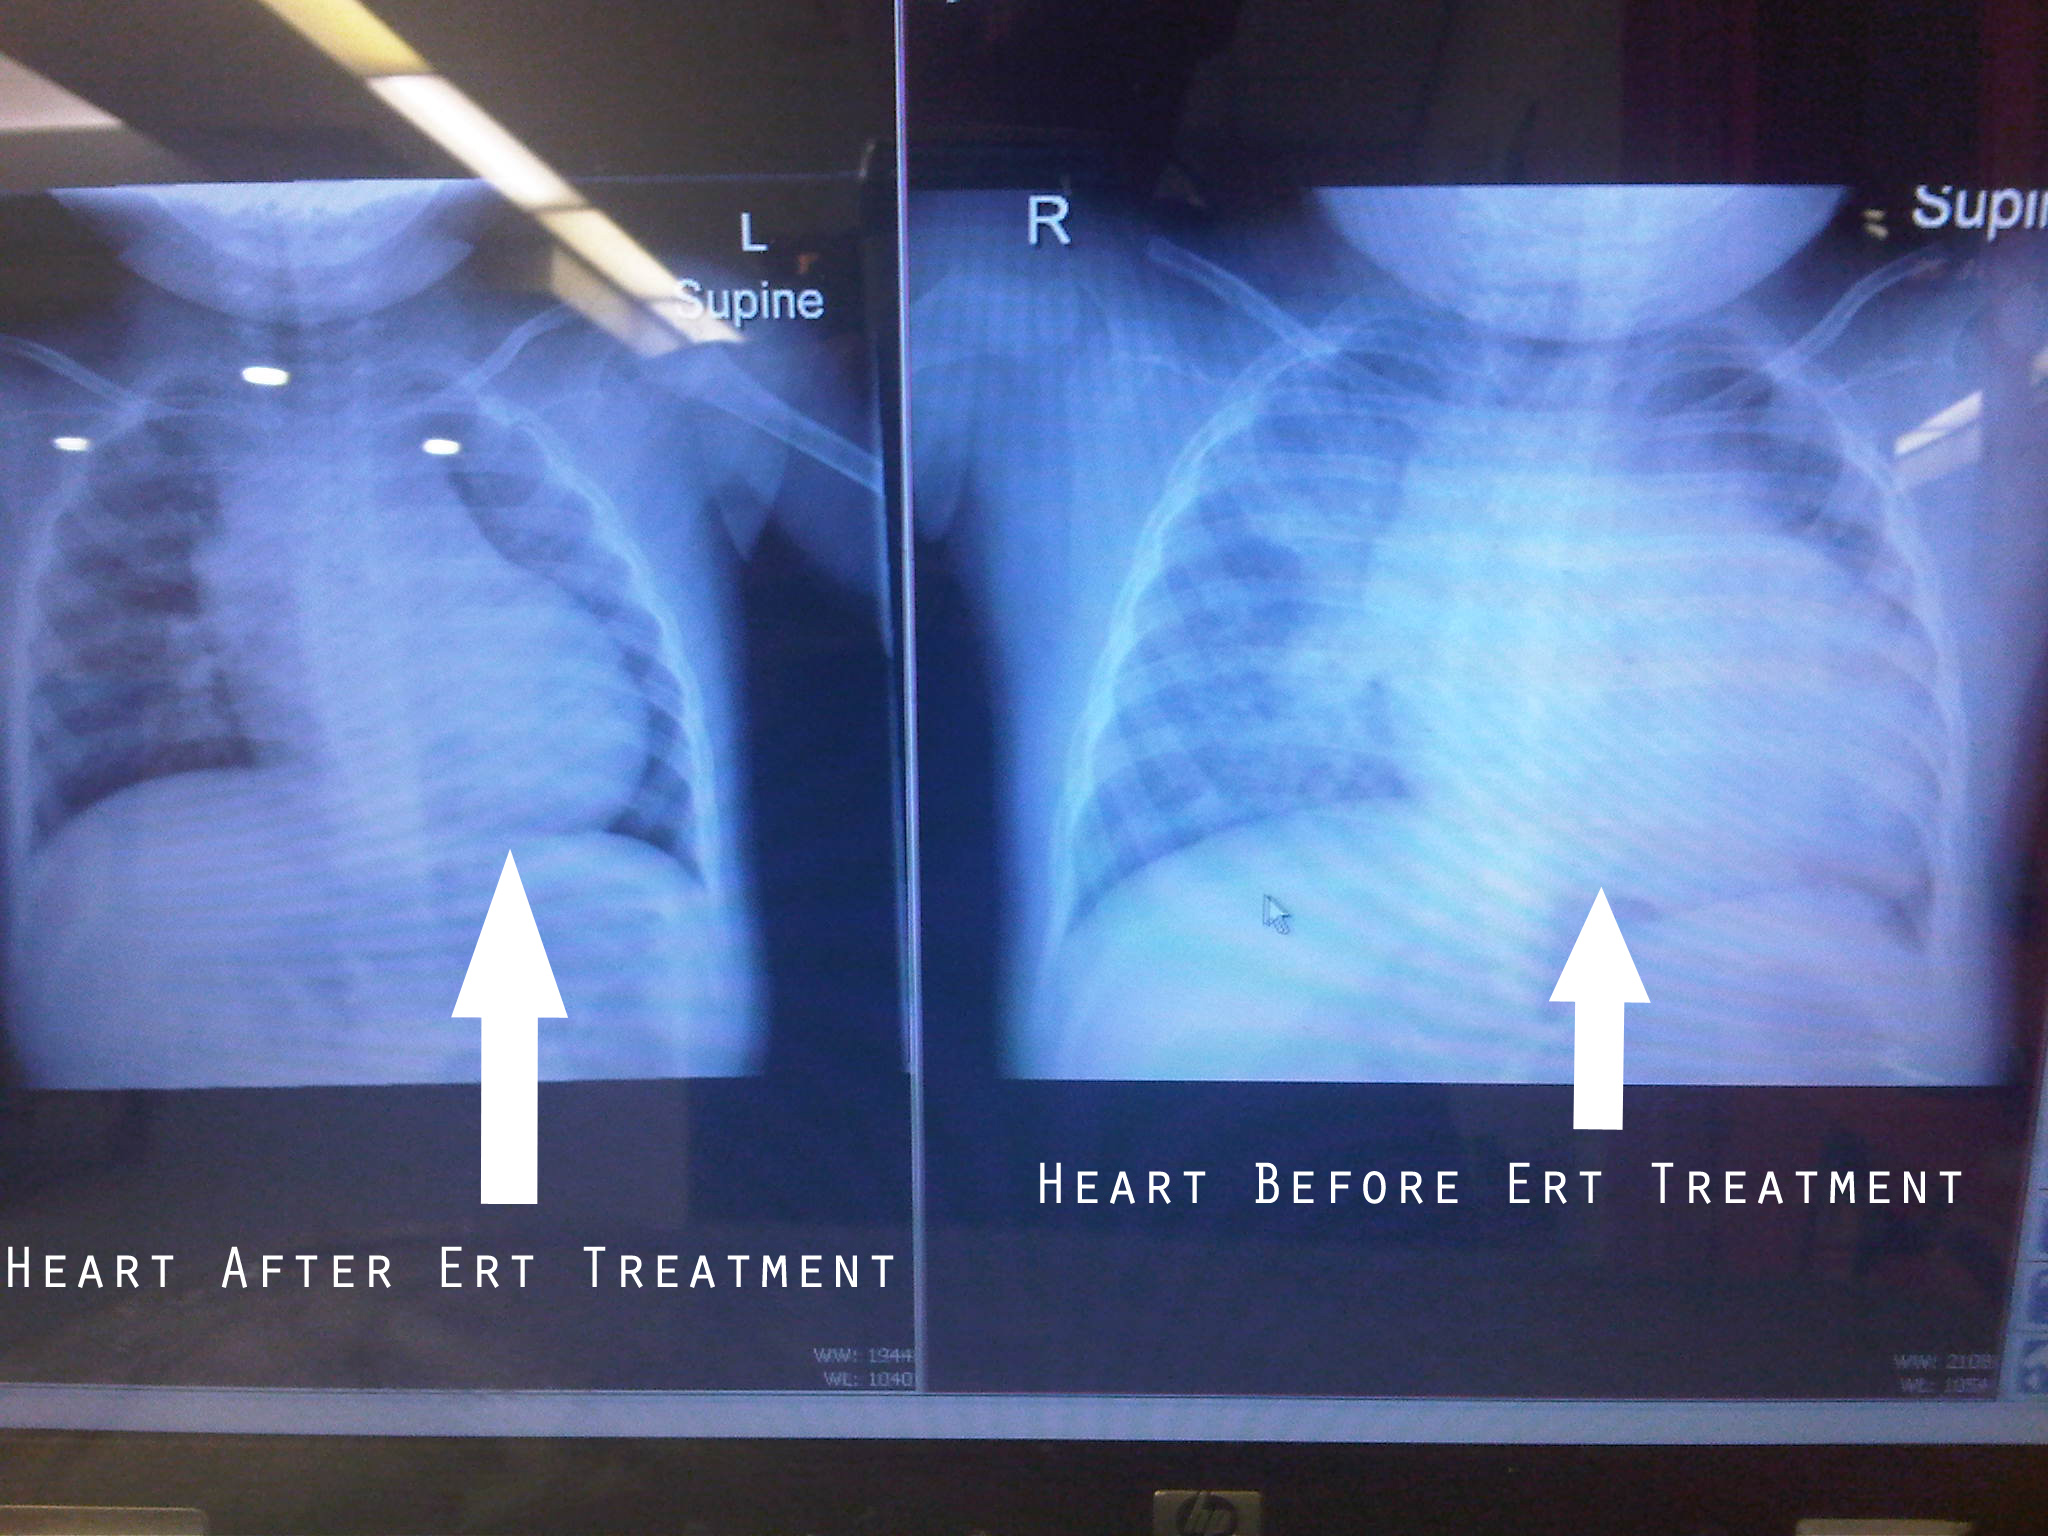

The paraspinal muscles that support your back usually show changes before other muscle groups. There was no change in cardiovascular status associated with enzyme replacement therapy. The incidence of pompe, reported in 1/40,000 patients worldwide, is quite rare. Ad creating individualized treatment plans for children with pompe disease.

Conduction abnormalities and ecg signs of ventricular hypertrophy are generally part of the disease spectrum. In infantile pompe disease, ecg typically depicts hypertrophic cardiomyopathy with or without left ventricular outflow tract obstruction in the early disease phase. Pompe disease is a genetic disorder in which complex sugar called glycogen builds up in the body’s cells. At present there is no known cure for pompe's disease and symptomatic treatment does not